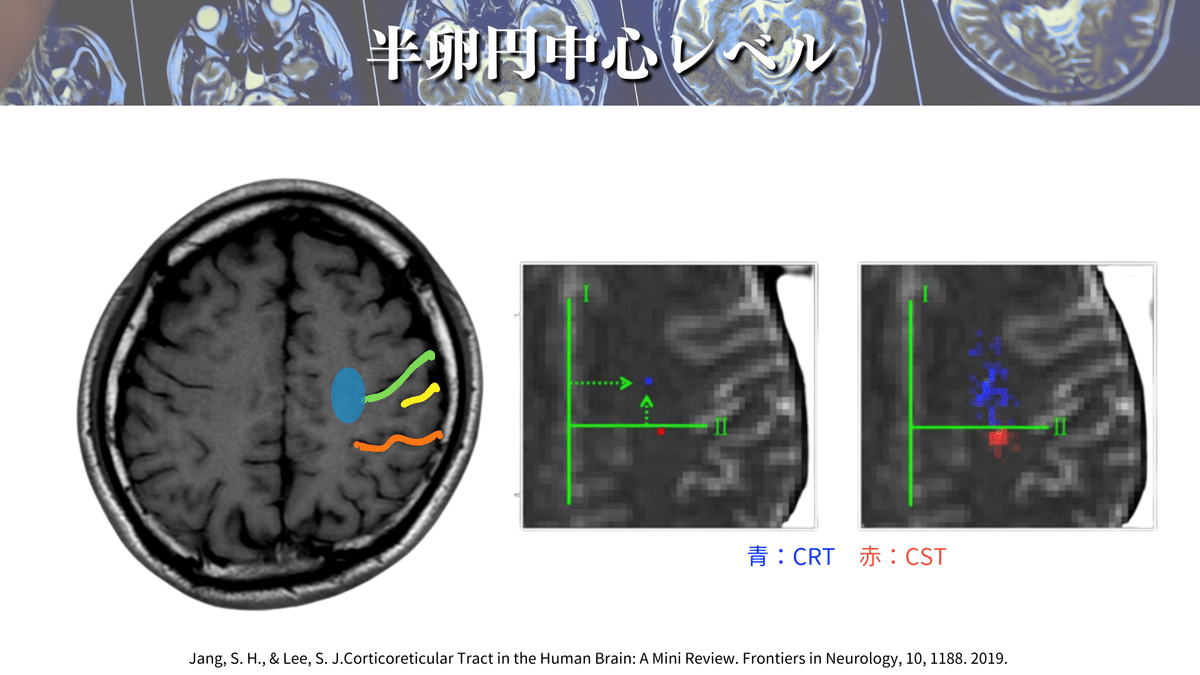

• 皮質網様体路の走行とMRI読影|サギョウ先生